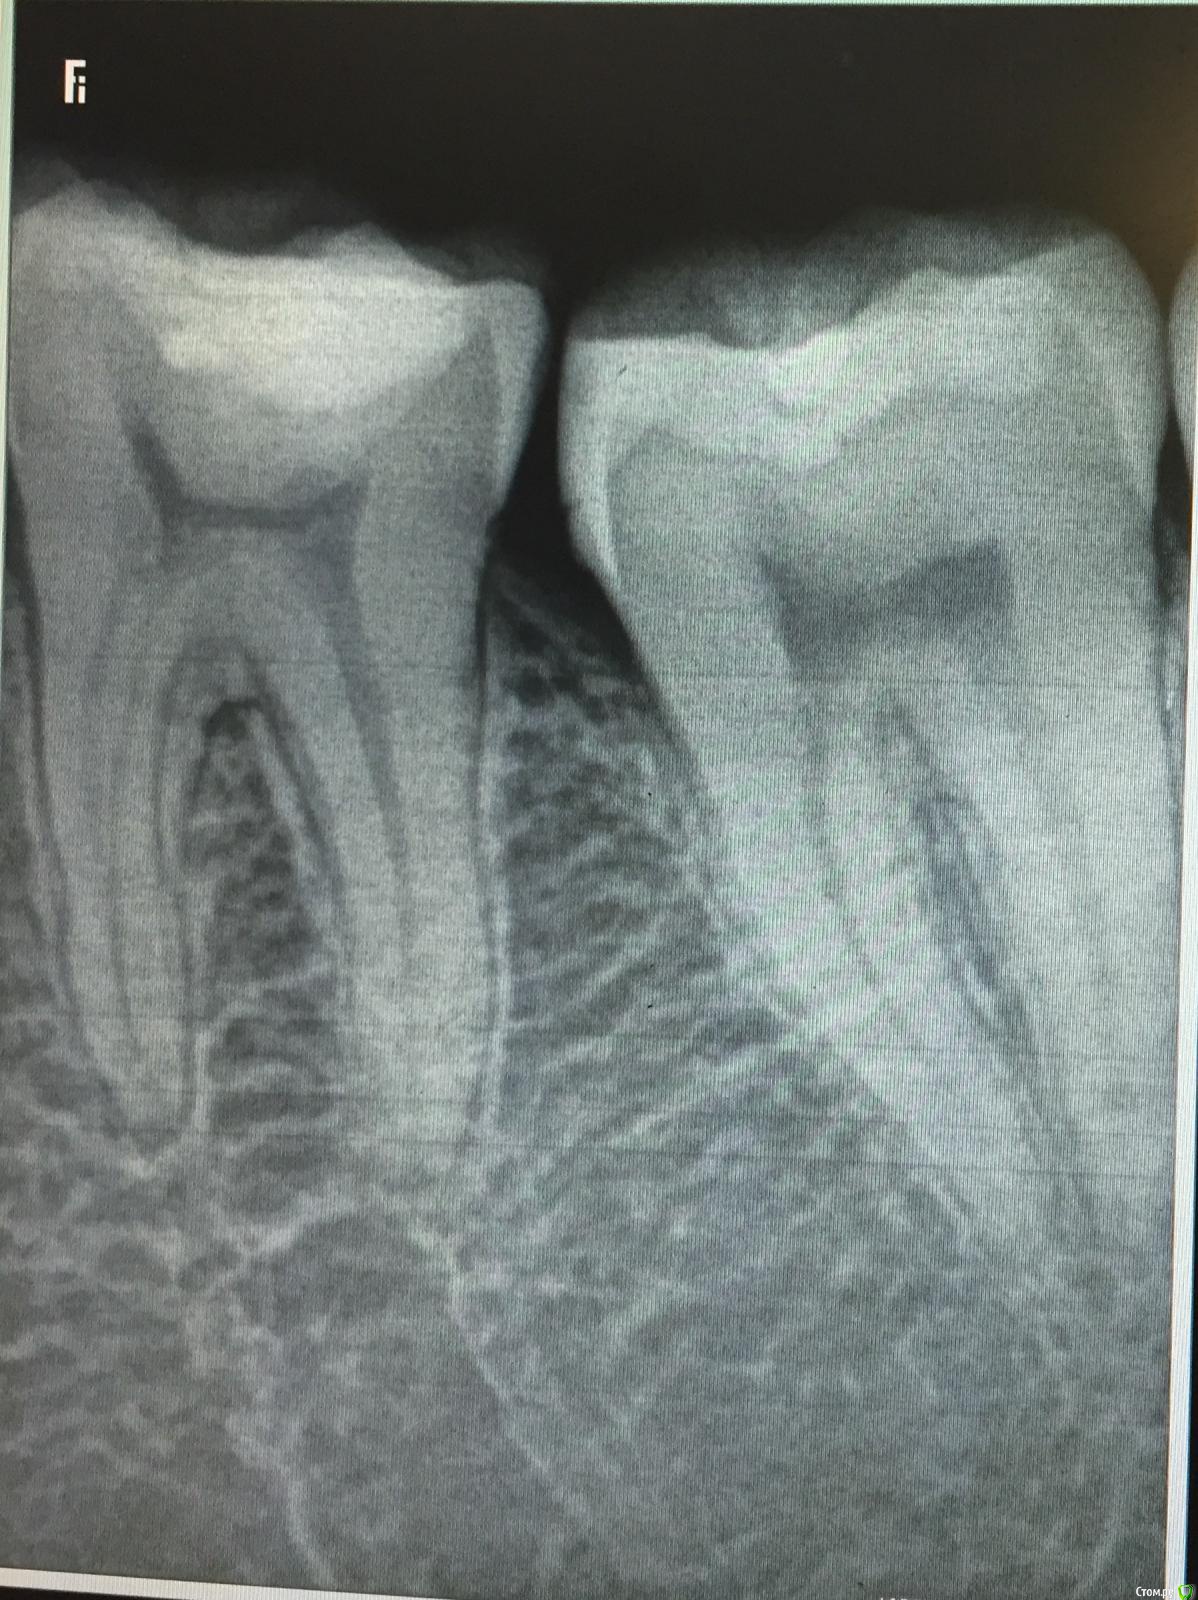

MariaK Опубликовано 30 марта, 2016 Поделиться Опубликовано 30 марта, 2016 Добрый день! Полтора месяца назад лечила пациентке зуб 37 по глубокому кариесу. Через пару дней она обратилась с жалобой, что пломба завышает. Убрала лишнее, заполировала, внешне все герметично. Вчера созванивались с ней, она говорит, что так же больно при накусывании, при попадании жесткой пищи. На горячее/холодное не реагирует. Сегодня подойдёт на приём. Думаю, стоит ли менять уже пломбу? Возможно, дебондинг?П.с. Плотного межзубного контакта не было и до лечения. Пища не застревает. Извиняюсь за качество снимка, с работы из уносить нельзя, пришлось фотографировать экран на телефон. Ссылка на комментарий

Карен Аванесов Опубликовано 30 марта, 2016 Поделиться Опубликовано 30 марта, 2016 Смотрите внимательно 3.6 зуб. 2 Ссылка на комментарий

___49___ Опубликовано 1 апреля, 2016 Поделиться Опубликовано 1 апреля, 2016 (изменено) Пользовался несколько раз при подобных жалобах кусочком резинки предназначенной для тяг при переломах - клал ее на пломбу и просил пожевать , а затем на участок без пломбы - реакцию давали на пломбу, решалось все заменой пломбы с соблюдением протокола протравки, сушки, нанесения бонда. Но я все равно при возможности проверил бы на витальность. Смущает состояние переодонта у верхушки медиального корня 6ки. Изменено 1 апреля, 2016 пользователем ___49___ 1 Ссылка на комментарий